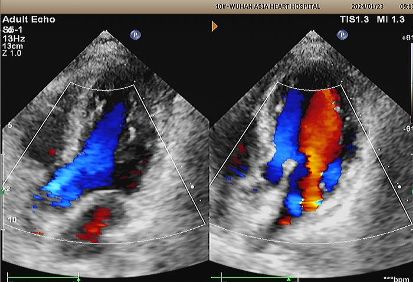

1-Year Echo:

No visible disc structures – replaced by 8mm tissue thickening at the septal implant site.

Zero residual shunt (rest or post-Valsalva).

Complete device absorption confirmed.